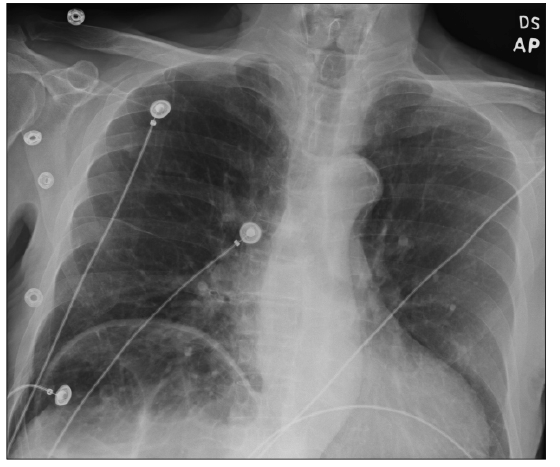

This article presents a case of a large PFO associated with ischemic stroke and reversible POS due to colonic distention resulting in the right hemidiaphragm elevation in the setting of obstipation.